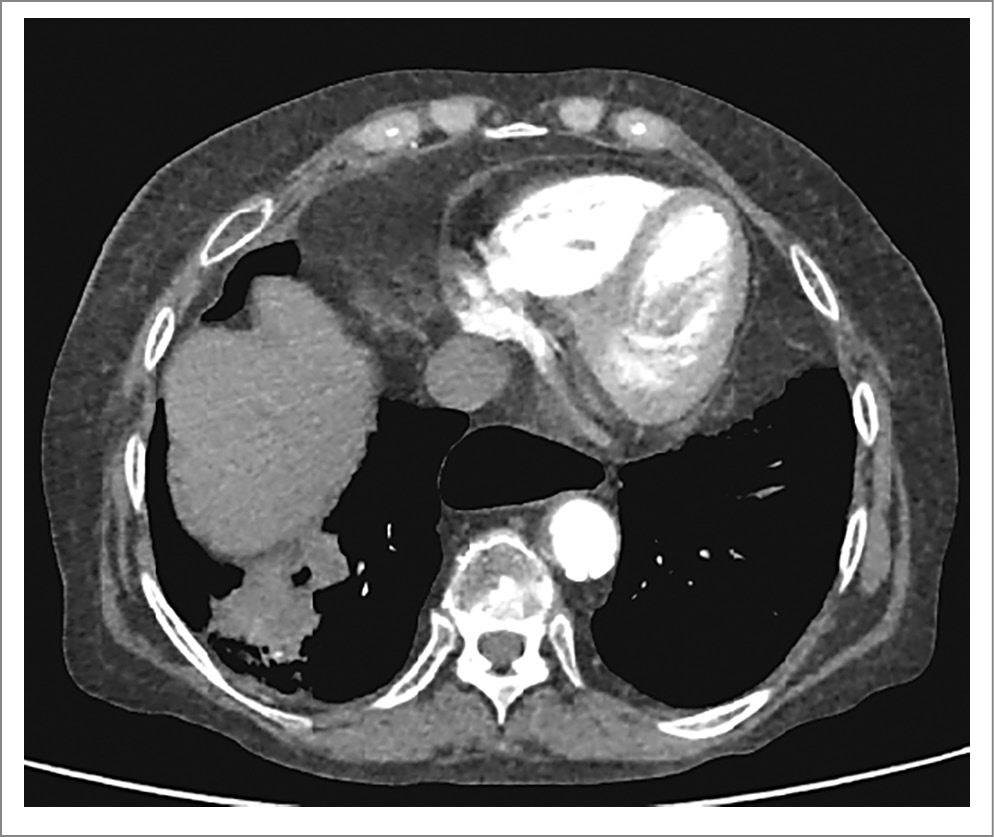

С целью дальнейшего онкопоиска выполнена МСКТ ОГК, брюшной полости и малого таза с внутривенным контрастированием. Выявленное при нативной КТ образование нижней доли правого легкого неравномерно накапливало контрастный препарат, что подтвердило его злокачественный генез. Контрастный препарат также накапливался в увеличенных лимфоузлах корня правого легкого, VII ребре справа и LV позвонке. В VI сегменте печени выявлено образование размером 7 мм, вероятно, вторичного характера (рис. 5).

Рис. 5. МСКТ ОГК с внутривенным контрастированием. Неравномерное накопление контрастного препарата в образовании нижней доли правого легкого.